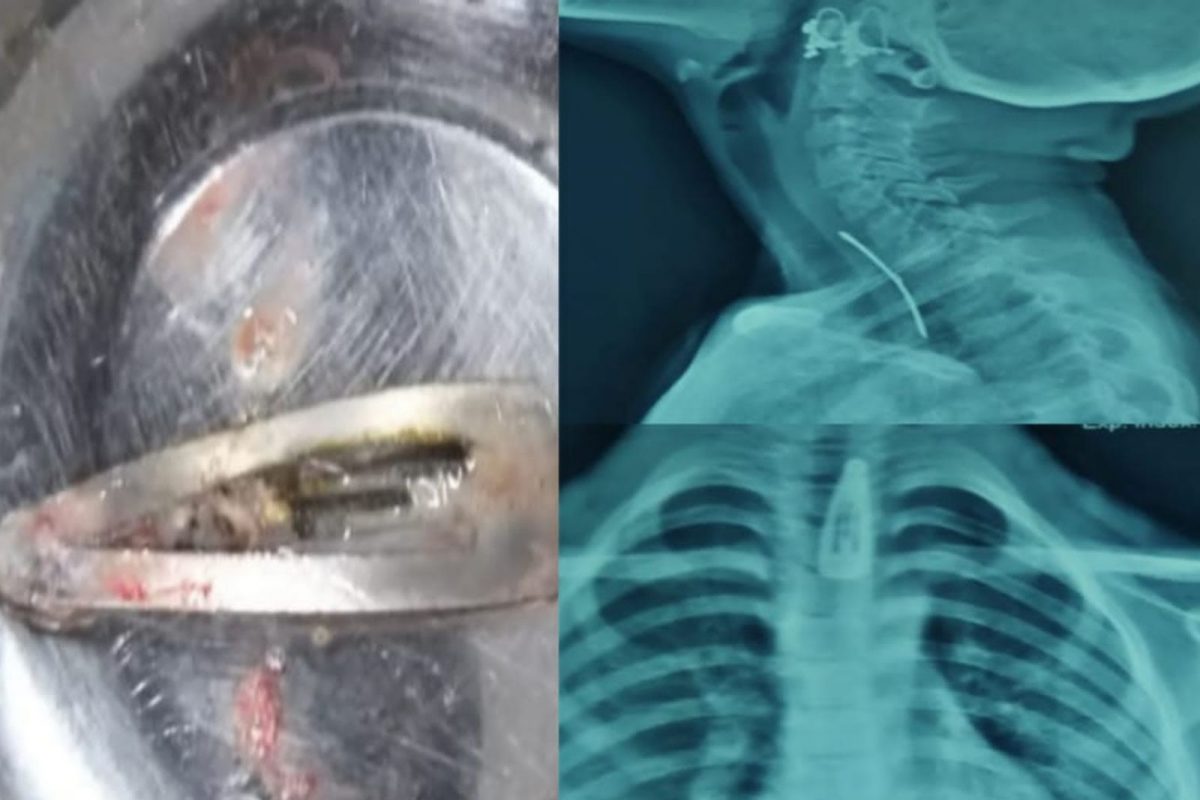

अमित राय/कोल्हापूर : कोल्हापूरातील एका सात वर्षांच्या बाळाने महिलांच्या केसातील पिन गिळल्याचा प्रकार समोर आला आहे. शस्त्रक्रियाद्वारे डॉक्टरांनी यशस्वीपणे ही पिन बाहेर काढली. बाळाला गिळताना आणि छातीत त्रास होऊ लागल्याने त्यांनी तात्काळ येथील सीपीआर रुग्णालयात दाखल केले होते. त्यानंतर एक्स-रे मध्ये बाळाने केसांतील पिन गिळल्याचे दिसून आले. त्यानंतर तत्काळ वेळ न घालवता डॉक्टरांनी दुर्बिणीद्वारे अन्न नलिकेतून ही पिन बाहेर काढली. जवळपास दीड सेंटीमीटर लांब ही पिन होती. सद्या बाळाची प्रकृती ठीक असल्याचे डॉक्टरांनी सांगितले आहे. अनेकदा लहान मुलांकडे थोडंही दुर्लक्ष केलं तरी महागात पडू शकतं. त्यामुळे पालकांनी अधिक सजग राहणं आवश्यक आहे. सेल, पिन किंवा आकाराने लहान वस्तू लहान मुलांच्या आजूबाजूला ठेवणं टाळावं. काही मुलं नाणी देखील गिळल्याच्या अनेक घटना समोर आल्या आहेत. सेलही गिळल्याच्या घटना समोर आल्या असून हे धोकादायक आहे. त्यातून अनर्थ घडू शकतो.

कोल्हापुरातील या घटनेत वेळेत बाळाला डॉक्टरांकडे नेल्याने त्याचा जीव बचावला आहे. त्याला गिळण्यास त्रास होत असल्याने याचा उलगडा झाला. एक्सरेमध्ये पिनचा आकारही दिसून येत आहे.